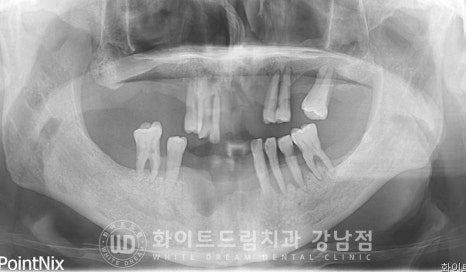

정말 많은 뼈이식재를 이용하여 잇몸뼈가 소실된 부위를 최대한 복원하며

진행한 치주염 전체임플란트 케이스였습니다.

환자분은 그나마 다행인 것이 정상 잇몸뼈가 일부분 있는 상태여서 뼈이식을 통해

잇몸뼈의 높이를 어느 정도 회복한 후 식립을 진행할 수 있었지만